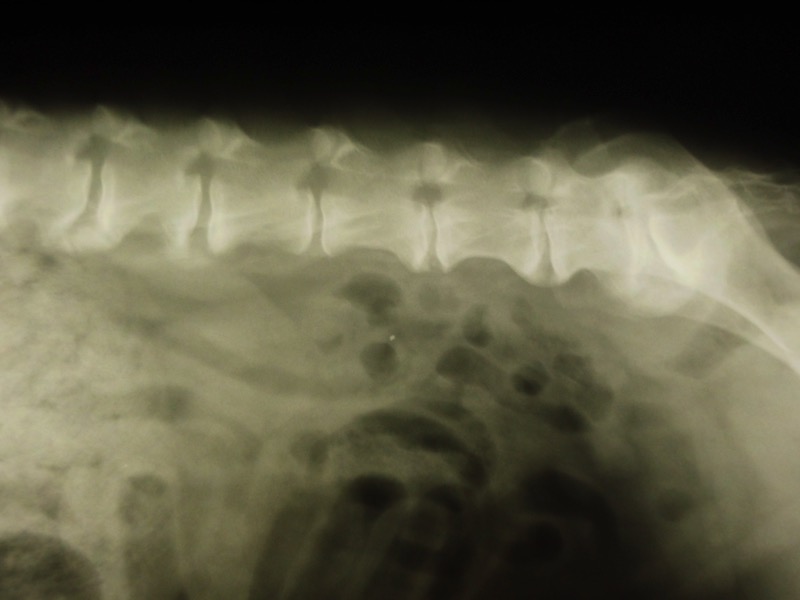

Bei Rolf gibt es leider keine Lösung. Er hat Spondylose, d.h. seine Wirbelsäule ist degenerativ verändert - leider im gesamten Verlauf. Rolf kommt damit klar. Er kann nur nicht mehr mit zu großen sportlichen Aktivitäten belastet werden.